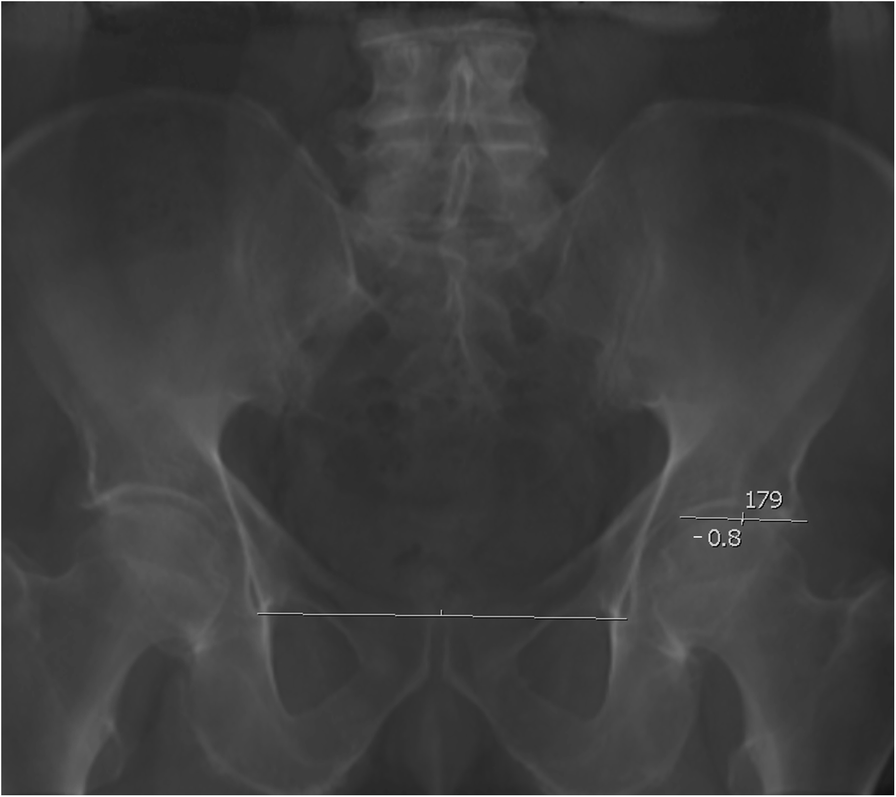

Fig. 1From: Correlation of radiographic variables to guide safe implant positioning during acetabular surgery and hip replacement: a retrospective observational studyMeasurement of the acetabular index on reconstructed 2D anterio-posterior views of the pelvisBack to article page